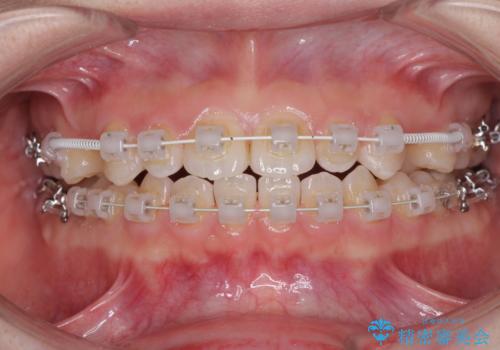

- 歯の欠損による隙間だらけの歯並びを気にして来院された患者様です。

上顎左右1本ずつ欠損していたため、歯列矯正により欠損部位にスペースを集め、その後欠損部位をインプラントにて補綴することとしました。

インビザラインによる矯正治療も提案しましたが、長時間の装着や自己管理が難しいとお考えで、ワイヤーによる矯正治療を行いました。

歯並びは比較的早めに整いましたが、インプラントを埋入するにあたって前後の歯根位置を改善する必要があり、矯正治療に期間を要することとなりました。